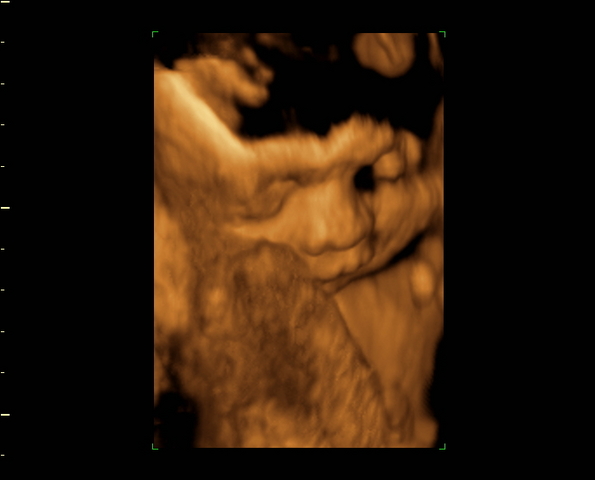

Juli, nagyon helyes gombóckád van!!!!

Csip, nekem augusztus 23-án fogant Hanna

nagyjából azonos időben fog a tied is születni